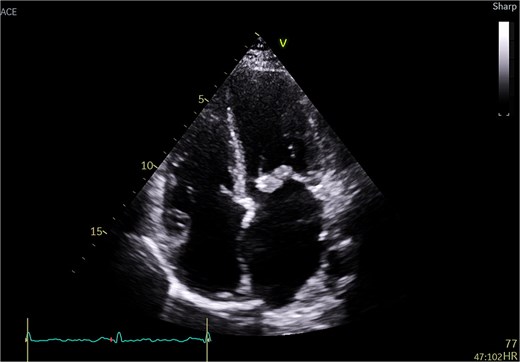

A 51-year-old woman with history of hypertension, hyperlipidemia, diabetes mellitus type II, previous ablation for supra ventricular tachycardia with implantation of loop recorder and sleeve gastrectomy for obesity was referred for surgical evaluation of MR. She was non-smoker with positive family history of ischemic heart disease affecting her mother. She was investigated for recurrent strokes with left sided paresthesia in 2022 and right sided paresthesia with dysarthria in 2024. She had dyspnea on minimal exertion and lower limb edema but no hemoptysis. She had one miscarriage previously with no history of deep vein thrombosis or pulmonary embolism. She had no history of myalgia, arthralgia, and no photosensitivity. Transthoracic echocardiography (TTE) showed pulmonary hypertension with moderate tricuspid regurgitation (TR) and moderate to severe MR and severe mitral stenosis (MS). The appearance was suggestive of rheumatic disease (Fig. 1). Trans esophageal echocardiography (TEE) showed severely dilated left atrium (LA) with no thrombus. Mitral valve with thickened with tethered posterior leaflet with mean gradient (MG) of 13 mmHg. Severe MS and moderate MR with large mass attached to the posterior scallops (Fig. 2) measuring 20 × 15 mm (likely thrombus). Ejection fraction was 55%. She was in sinus rhythm persistently and afebrile. Coronary angiography was normal. She was commenced on oral anticoagulation (Warfarin) for the possible thrombus, and she was reluctant for surgery. Her blood work was normal including normal complete blood count and renal, liver, and thyroid profile with therapeutic international normalized ratio (INR). Blood cultures were negative for growth. She was seen by haematology and work up revealed APS with a recommendation for lifelong warfarin. Patient subsequently accepted surgery.

Transesophageal echo appearance of mass attached to posterior leaflet of mitral valve (mid esophageal 4 chamber view).